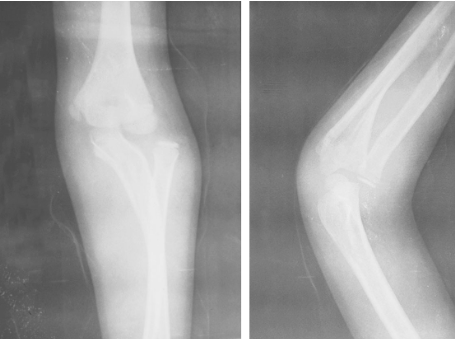

主诉:因“坠伤左肘部肿痛、活动受限6个小时”于2006年9月18日入院。约于6个小时前从行驶的摩托车后坐上坠地,致伤左肘部。当时局部肿痛、畸形、活动受限,手部感觉运动正常,遂至当地县人民医院就医,拍摄X线片(图1)示左尺骨近端骨折,向外成角移位,桡骨小头向外明显移位,诊断为左孟氏骨折,拟给予切开复位内固定术,为进一步治疗转诊我院。

图1 伤后3小时X线片

影像学检查:拍摄前臂全长X线片(图2),左尺骨近端骨折,向外成角移位,桡骨小头向外明显移位;尺、桡远端骨折,骨折波及骨骺线,远折块一致性向桡背侧移位,桡骨远折端向近侧压缩移位明显,尺、桡骨远端间隙增大。

图2 伤后6小时X线片